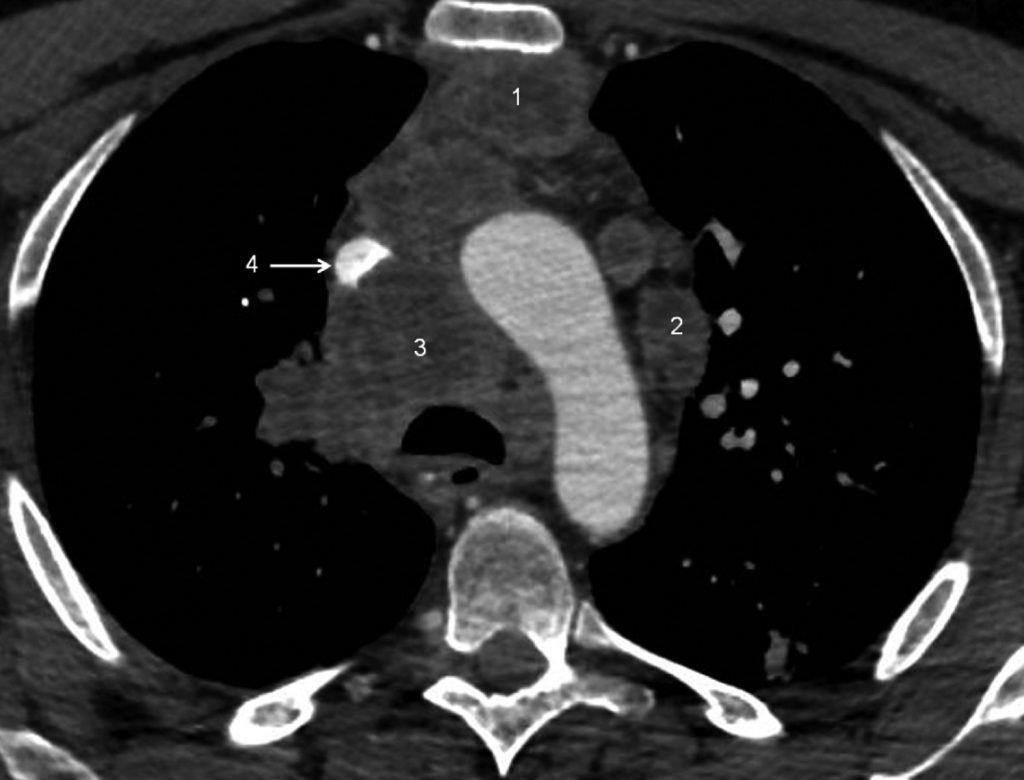

Fig. 101.3. Scanner thoracique.

Multiples adénomégalies médiastinales partiellement nécrotiques intéressant la loge thymique (1), la chaîne para-aortique (2) et la chaîne paratrachéale droite, ou loge de Barety (3). Sur cette coupe, la veine cave supérieure (4) apparaît partiellement laminée par les adénopathies mais reste perméable. Il s’agissait d’un carcinome à petites cellules.

Source : CERF, CNEBMN, 2022.